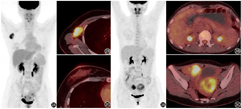

PET/CT上转移灶明确且代谢高,而原发灶"隐匿"的情况并不十分罕见,主要原因是原发灶比较小,阅片时可能被忽略;或原发灶位于周围本底摄取较高的区域,被"掩盖"了;再或者原发灶和转移灶的分化或某些病理特征不同,代谢程度有较大差异。这时,一要仔细观察有较高本底摄取的脏器或部位并采集相关病史,来除外此处肿瘤发生转移(如泌尿系统[1]、肠道、肝脏、口咽部等);二要根据转移模式和病理类型推定可能的原发灶,如出现锁骨上淋巴结转移或腋窝淋巴结转移或骨转移的腺癌需要进一步筛查前列腺癌及乳腺癌,有腹膜转移或腹腔积液的腺癌需要警惕泌尿生殖系统、胰腺及胆道系统原发肿瘤,有肝脏转移的腺癌需进一步检查消化道系统、胰腺及胆道系统、乳腺来源的肿瘤,全身多发转移的腺癌需重点考虑前列腺癌及乳腺癌,头颈部淋巴结或锁骨上淋巴结转移的鳞状细胞癌(简称鳞癌)需重点关注头颈部肿瘤,纵隔淋巴结转移的鳞癌需重点筛查非小细胞肺癌等。如图2为1例右侧腋窝淋巴结转移患者,临床高度怀疑乳腺癌转移,而PET/CT上乳腺未见异常代谢,CT也未见明确占位;随后乳腺超声见右乳内下象限乳腺影像报告和数据系统(breast imaging reporting and data system, BI-RADS) 4b级病变,患者遂行右乳肿物扩大切除术及右腋窝淋巴结清扫术,术后病理提示右乳低分化浸润性癌,伴右腋窝淋巴结转移。图3为1例胃癌伴双侧卵巢转移患者,PET/CT见双侧卵巢转移灶代谢明显增高,而胃壁代谢未见明显异常(胃镜见胃体大弯侧溃疡)。